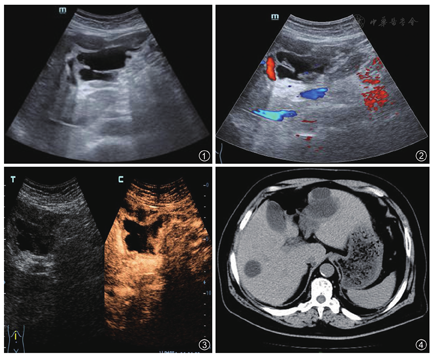

二维超声声像图示:肝脏大小及形态正常,肝内可见多发圆形、类圆形无回声区,壁薄、光滑、内清晰,后方回声增强。肝左叶边缘可见大小6.9 cm×4.2 cm混合性回声(图1),囊内可见少许分隔,无血流信号(图2),囊壁增厚、回声紊乱。下腹肠间可见较厚径7.3 cm无回声区。

超声造影检查:经肘正中静脉团注入Bracco公司SonoVue微泡超声造影剂1.8 ml,实时观察肝左叶内囊实性病灶3 min,15 s造影剂开始充盈,32 s充盈均匀,46 s开始消退,动脉相、门脉相、延迟相囊腔内均未见造影剂充盈,囊壁强化程度始终与肝实质保持同步,病变周围腹腔内未见造影剂信号(图3)。

平扫计算机体层摄影(computed tomography,CT):肝大小、形态未见异常,被膜光整,肝内可见多发类圆形、不规则低密度影,边界清晰,较大者位于肝左叶边缘,密度均匀,周围脂肪间隙模糊,可见斑片状密度增高影,其余肝实质密度均匀(图4)。右侧结肠旁沟、盆腔内可见片状水样密度影。